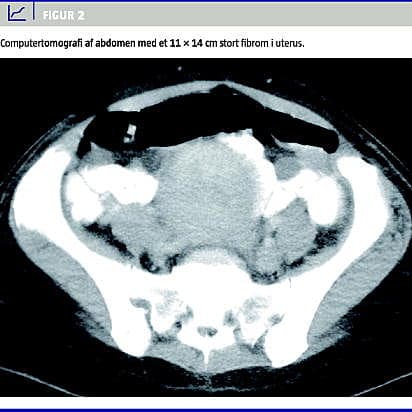

Ved CT af abdomen genfandt man en 11 14 cm stor ensartet proces i uterus (Figur 2 ), minimal ascites samt hyperekkogene processer i leveren, der initialt blev beskrevet som metastasesuspekte, men senere tolkedes som hæmangiomer. Leukocytskintigrafi var uden sikre opladninger. Da patienten fortsat var diagnostisk uafklaret, bestiltes helkropspositronemissionstomografi (PET).